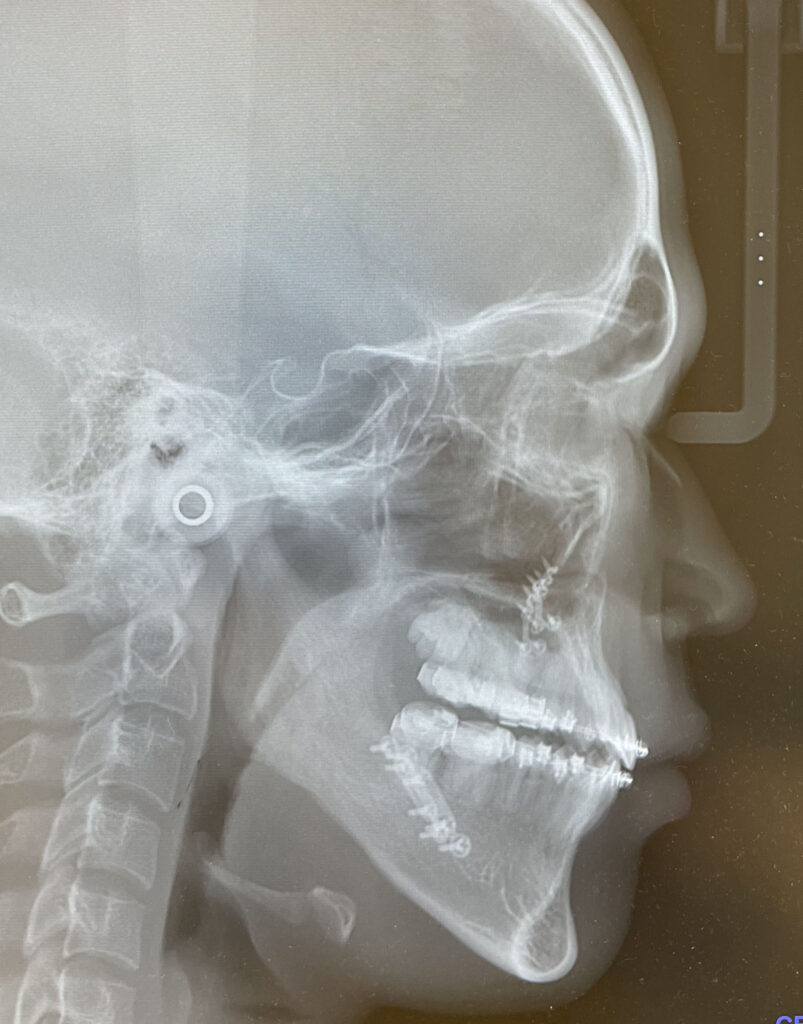

術前後のセファログラムを以下に示します。

手術は、上顎に対してLe Fort I型骨切り術、下顎に対して下顎枝矢状分割骨切り術(SSRO)を施行しました。

顔面高を減じる目的で上顎を上方移動させ、さらに開咬を確実に閉鎖するため、上顎骨・下顎骨複合体を時計回転させる術式を選択しました。

下顎前突は改善され、骨格的なバランスが整いました。また、開咬も解消し、安定した咬合が得られています。